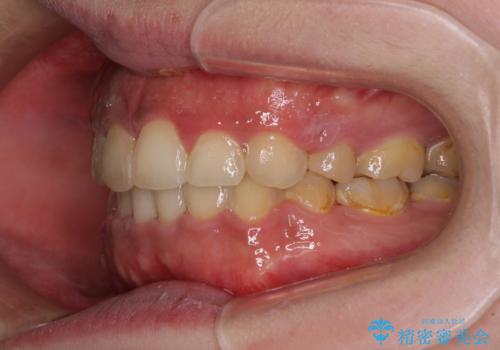

- 審美装置

- 口元の突出感と上下前歯のでこぼこを気にして来院された患者様です。

上下前歯部叢生のスペース獲得のため、上下顎左右小臼歯各1歯(計4本)を抜歯して、矯正治療を行うこととしました。

口腔内の清掃性に問題があり、虫歯のリスクが極めて高かったため、短期で治療を終えることを最優先に治療を進めました。